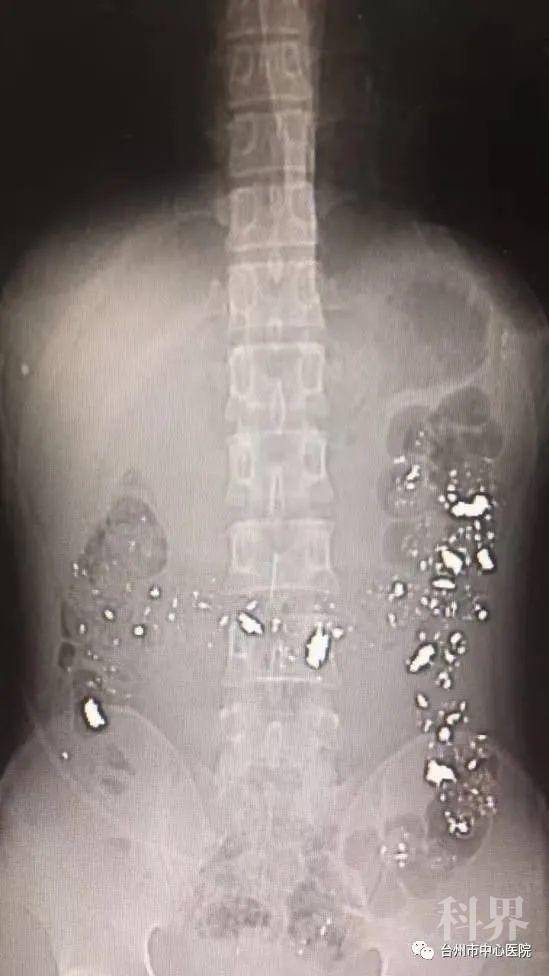

腹部CT片